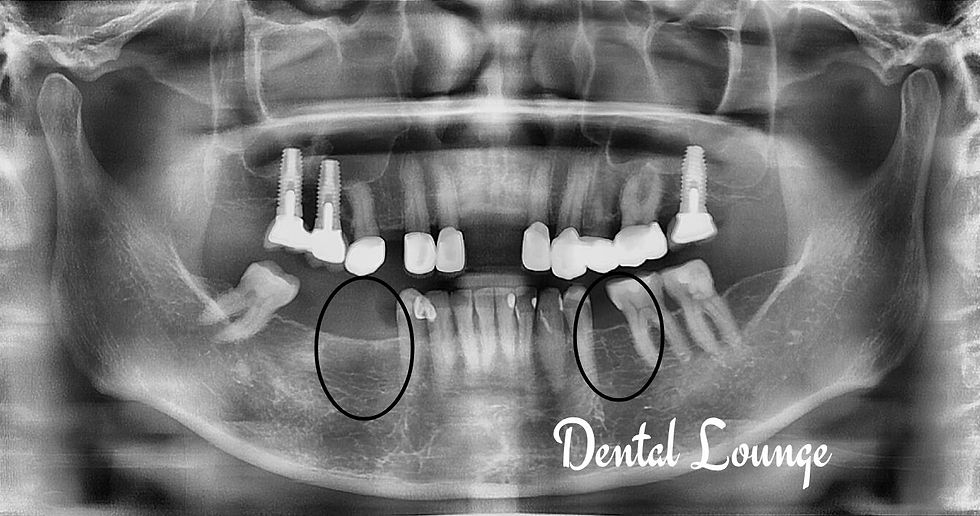

Surgical Removal of Impacted #48 with Extraction of #47 Due to Advanced Caries and Periodontal Bone Loss

Patient presented with pain from impacted lower wisdom tooth causing distal decay and bone loss in adjacent molar. Surgical removal of impacted tooth and extraction of compromised molar performed successfully with nerve structures preserved.